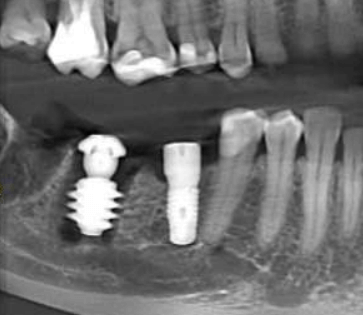

В область отсутствующей шестерки был установлен AnyOne Onestage Tussue Level, а в лунку моляра – широкий AnyRidge + мультиюнит с высотой десны 2,5 мм. Далее пластика мягких тканей.